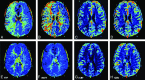

Results: Among 1850 MR imaging studies, 20 (1.08%) patients were found to have acute migrainous aura. Hypoperfusion was found in 14/20 patients (70%) with delayed rMTT and TTP, decreased rCBF, and minimal decrease in rCBV. In contrast to the typical pattern in stroke, perfusion abnormalities were not limited to a single vascular territory but extended to >1. Bilateral hypoperfusion was seen in 3/14 cases. In 11/14 cases, hypoperfusion with a posterior predominance was found. TTP and rMTT were the best maps to depict perfusion changes at visual assessment, but also rCBF maps demonstrated significant hypoperfusion in quantitative analysis. In all patients, clinical and imaging follow-up findings were negative for stroke.